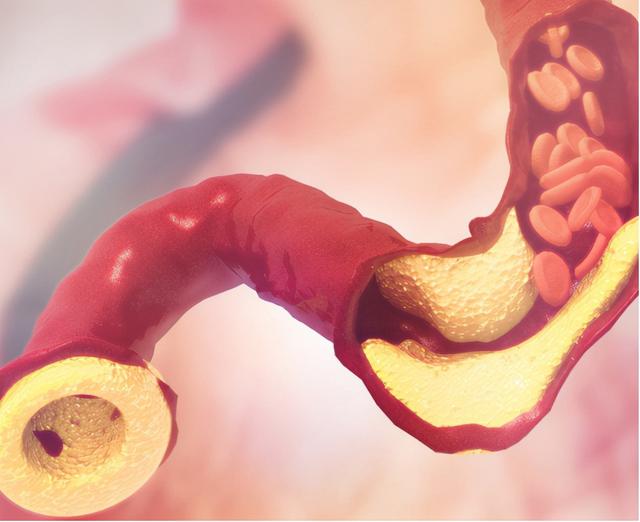

2. 脑梗死。由于动脉粥样硬化,导致血管发生堵塞,脑供血状况异常,从而引起了脑梗死。脑梗死的患者会有身体感觉异常,共济失调,头晕头疼以及眩晕等。随着病情的进一步加剧,则会大大影响到患者生命安全。因此,个人必须要加强防范意识,多注意身体变化。

3. 缺血性脑病。长期慢性脑供血不足,容易引起头晕头昏,乏力等症状,患者脑部血管容易发生梗塞,使得患者出现记忆力下降,判断力失常以及行为异常。伴有缺血性脑病的人,不及时治疗的情况下,会逐渐演变成痴呆,老年朋友应提高警惕。